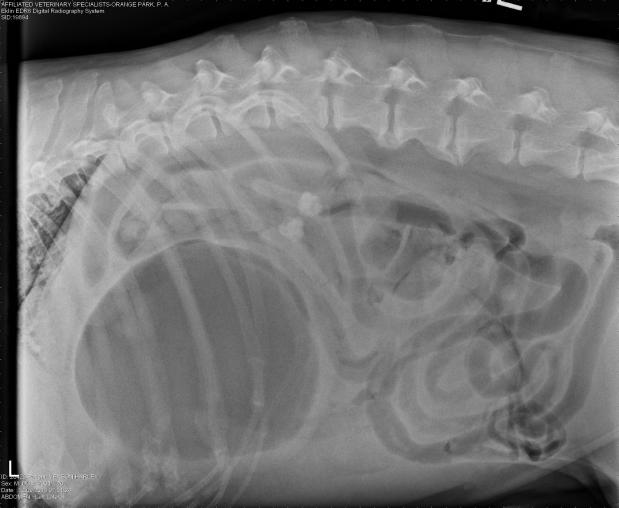

An experienced veterinarian will be able to quickly diagnose this condition, based on signalment (breed), clinical signs, and physical examination. Radiographs (X-rays) generally leave little doubt, as there are “tell-tale” signs seen on x-rays. Blood work will also be performed to assess values such as red blood cell concentration, electrolyte abnormalities, lactate, etc all factors that will be used to guide initial stabilization and treatment prior to surgery. Once diagnosed, surgery is required. If surgery is not feasible (patient is not able to be stabilized, owner unable to move forward with surgery, etc), humane euthanasia will be likely recommended.

This is a right lateral abdominal x-ray. Note the large, dilated stomach and evidence of the duodenum (intestine) just above the stomach and below the spinal column.